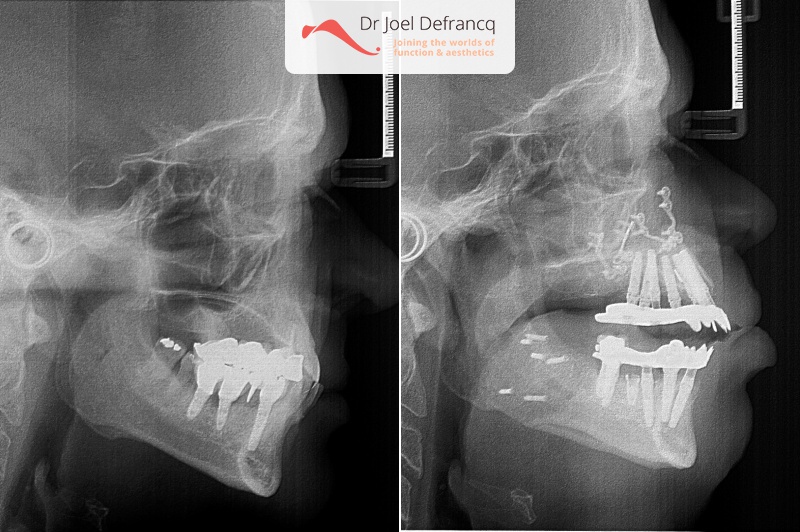

Behandeling tandheelkundige implantaten

- Vaste tanden op implantaten (bovenkaak)

- Vaste tanden op implantaten (onderkaak)

- Met bi-maxillair advancement